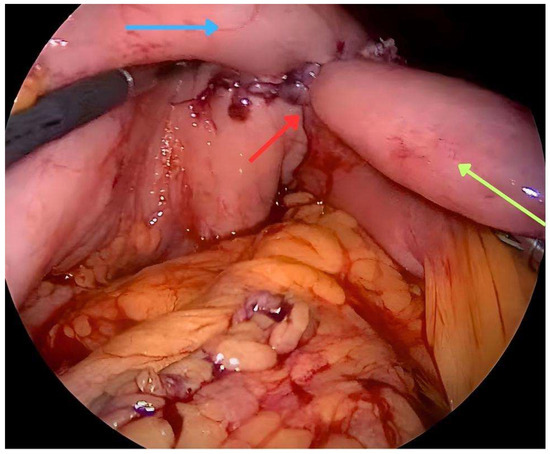

2. Surgical Gastrojejunostomy Techniques

3. Endoscopic Enteral Stenting